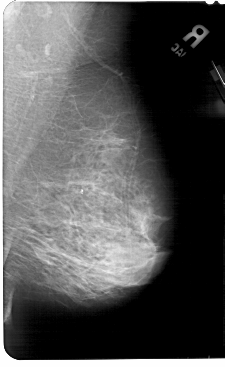

A_1496_1.LEFT_MLO

LEFT_MLO LINES 5491 PIXELS_PER_LINE 3346 BITS_PER_PIXEL 12 RESOLUTION 43.5 OVERLAY